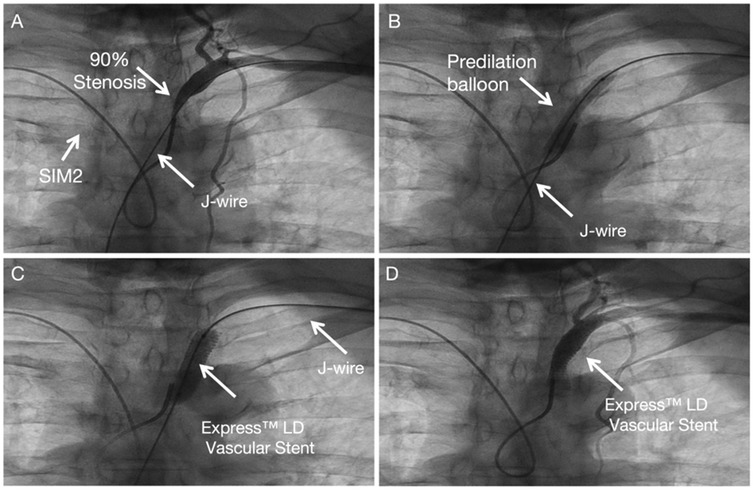

SIM 2 catheter from right-hand access engaged in the proximal cap of left subclavian artery stenosis and J wire from the left hand across left subclavian artery stenosis (Figure 3A). Balloon angioplasty was performed with a Aviator 5.0 × 15 mm at 8 atm (Figure 3B). An Express™ LD Vascular Stent 8.0 × 27 mm was delivered without a guide catheter, positioned across the lesion and deployed at normal pressure (10 atm) (Figure 3C). Stent expansion, vessel wall apposition, and the absence of edge dissection were confirmed by angiography from SIM2 and showed mild residual stenosis only (Figure 3D). Technical details are available in the Supplementary Materials 1, 2.

Figure 3. Subclavian stenting procedure method of left Non-CTO subclavian stenosis. (A) Engagement of the proximal lesion with a catheter from the right access and a wire from the left access. (B) Balloon angioplasty. (C) Stent deployment. (D) Final angiogram showing good stent expansion with only mild residual stenosis.